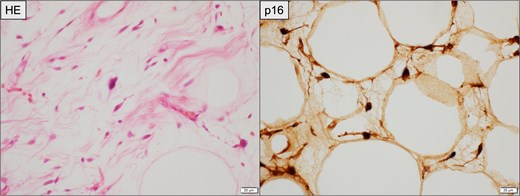

Histopathological findings of the primary retroperitoneal tumor. Left: Hematoxylin and eosin (HE) staining showing spindle-shaped atypical cells with abundant collagenous stroma suggestive of WDLPS. Right: Immunohistochemical staining for p16, demonstrating diffuse nuclear and cytoplasmic positivity in tumor cells. Scale bar = 20 μm.